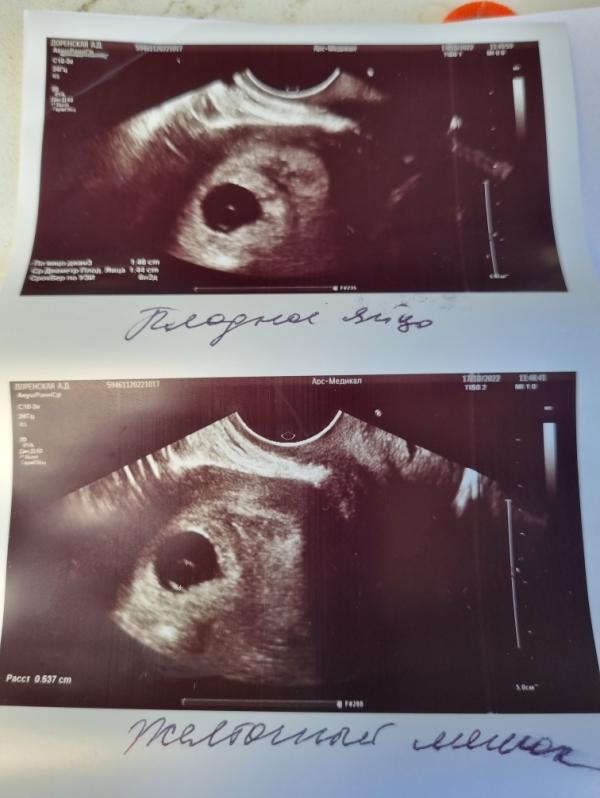

Привет, девочки, позвонили мне с клиники, сказали приехать. Приехала. Она мне опять сделала узи. Желточный мешок есть (5.4мм) сказала, что не указала его, потому что он не имеет значимости🙈 эмбриона нет, пульсации нет! Сказала, что уже должна быть. Подозрение на анэмбрионию. Через неделю повтор узи. Если ничего не появится, то на чистку... Я в шоке, не знаю что делать... За 4 дня ничего не выросло сказала...

У меня есть плодное яйцо, которое растёт и желточный мешок есть, а эмбриона и пульсации нет... По месячным 8 недель, по узи 6 нед 2 дня